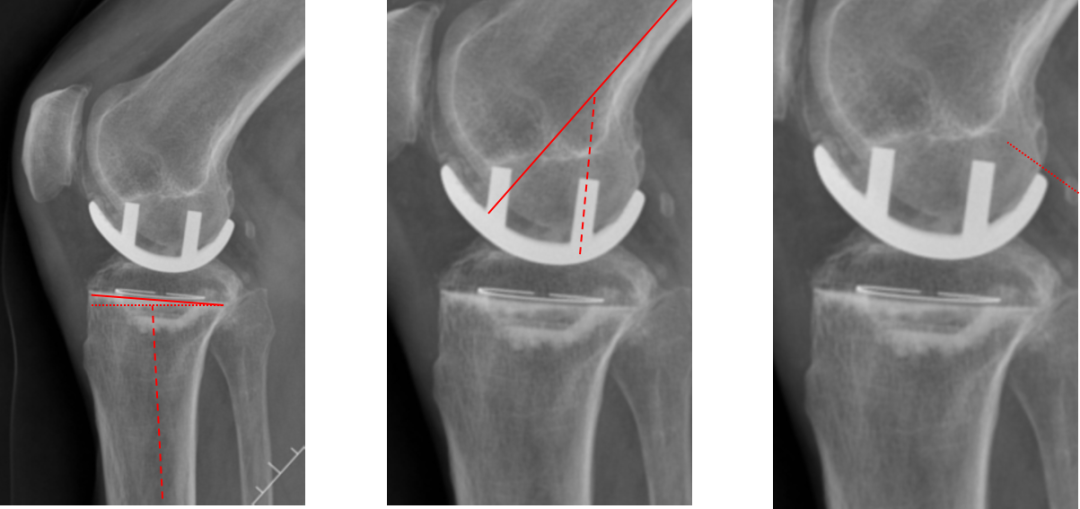

假体位置分析

正位片标准胫骨和股骨假体位置

AP位假体位置:胫骨假体轻度外翻,外侧缘与胫骨平台外侧缘齐平; 股骨假体长轴与胫骨假体垂直,与胫骨假体中线一致。

侧位片标准胫骨和股骨假体位置

侧位片假体位置:股骨假体后倾38°,假体后缘与股骨后髁齐平,胫骨假体后倾3°,与胫骨平台前后缘齐平。

标准胫骨和股骨假体位置

胫骨假体厚度合适

胫骨垫片厚度合适:术前外翻畸形基本矫正,残留2-3°外翻

胫骨假体后倾角度大

侧位片胫骨假体位置:胫骨假体后倾15°,前后缘齐平。

股骨假体偏小

侧位片股骨假体位置:股骨假体偏小,与胫骨假体后缘不齐平;屈曲35°,未包容股骨后髁。

股骨假体偏内放置

AP位胫骨与股骨假体位置:股骨假体中轴线与胫骨假体中线不一致,偏内侧,且外翻。

股骨假体偏外放置

AP位胫骨与股骨假体位置:股骨假体中轴线与胫骨假体中线不一致,偏外侧,且内翻